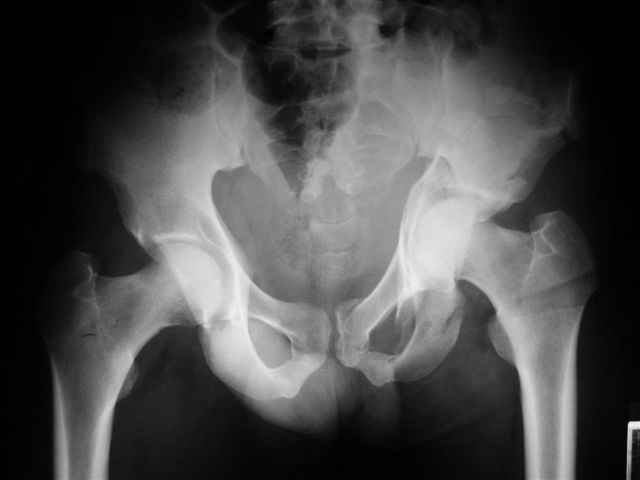

Спасибо за комментарии и рекомендации. Откровенно говоря, больного я прооперировал на прошлой неделе, через 5 дней после аварии и проблем с ним пока никаких нет, на удивление при достаточно обширной диссекции (илиофеморальный доступ) болей практически нет, так что больной самостоятельно садится в кровати, выполняет активные движения в оперированном суставе, сгибая до 60 градусов пока, далее с ассистенцией.

Причиной обращения к сообществу были возникшие непосредственно после операции сомнения и разочарования полученным качеством репозиции: а надо ли было трогать перелом вообще, репозиция передней колонны технически была очень сложна для меня, хотя реконструкции была в той же последовательности, что Д-р А.В.Рунков рекомендовал, в какой-то момент безуспешных манипуляций стал думать о *вторичной конгруэнтности*, которую не так давно обсуждали на

форуме и скелетном вытяжении. С репозицией и фиксацией задней колонны и отдельно задне-верхней стенки впадины проблем не возникло. Послеоп. Рг граммы в приложении. Если возникнут какие-либо дополнения или поправки - был бы признателен.